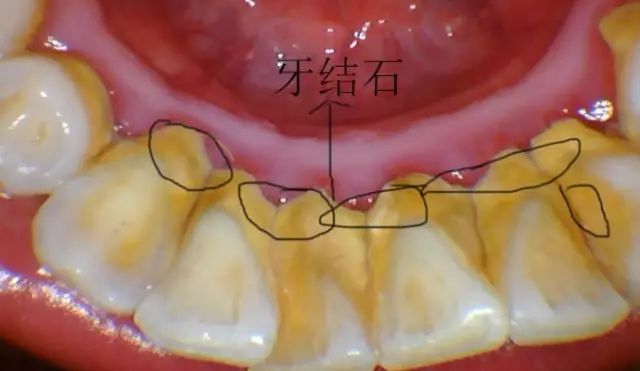

对于牙结石较多较厚、药物抗炎效果欠佳或脱敏治疗欠佳的患者,做一次对这些患者来说,太辛苦,而分几次洁牙,“化整为零”,患者容易接受,而且在洁牙间期,还可继续进行抗炎治疗或脱敏治疗,这可大大减轻酸痛感。

4、定期洁牙

长年累积的牙结石又多又硬,以致洁牙时需加大洁牙机的强度才能去除,这样会加重牙齿酸痛感。半年、一年或两年定期洁牙,在牙结石小的时候,形成的量不多,质较松,很容易去除,这样定期洁牙,就不易造成洁牙时的酸痛感。

洗牙后之所以让人容易有牙缝变大的感觉,是因为在洗牙的过程中,把堆积在牙龈表面、牙缝间的牙结石通过超声波震动方式震碎、清除,而使得舌头在碰触牙齿时,不再受到牙结石干扰,可直接碰触牙缝所致。其实,这些牙缝是本身早已存在的,与洗牙并无关。